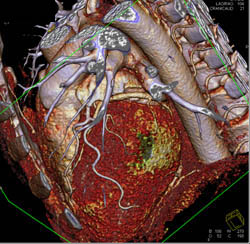

Normal Aortic Root